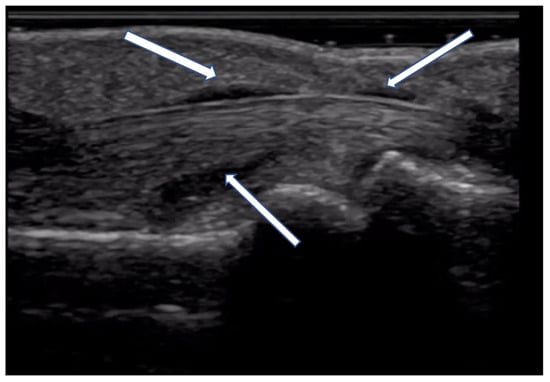

2.2.2. Contractures and Tendon Friction Rubs

- Tagliafico, A.; Panico, N.; Serafini, G.; Ghio, M.; Martinoli, C. The thickness of the A1 pulleys reflects the disability of hand mobility in scleroderma. A pilot study using high-frequency ultrasound. Eur. J. Radiol. 2011, 77, 254–257. [Google Scholar] [CrossRef]

- Stoenoiu, M.S.; Houssiau, F.A.; Lecouvet, F.E. Tendon friction rubs in systemic sclerosis: A possible explanation--an ultrasound and magnetic resonance imaging study. Rheumatology 2013, 52, 529–533. [Google Scholar] [CrossRef]